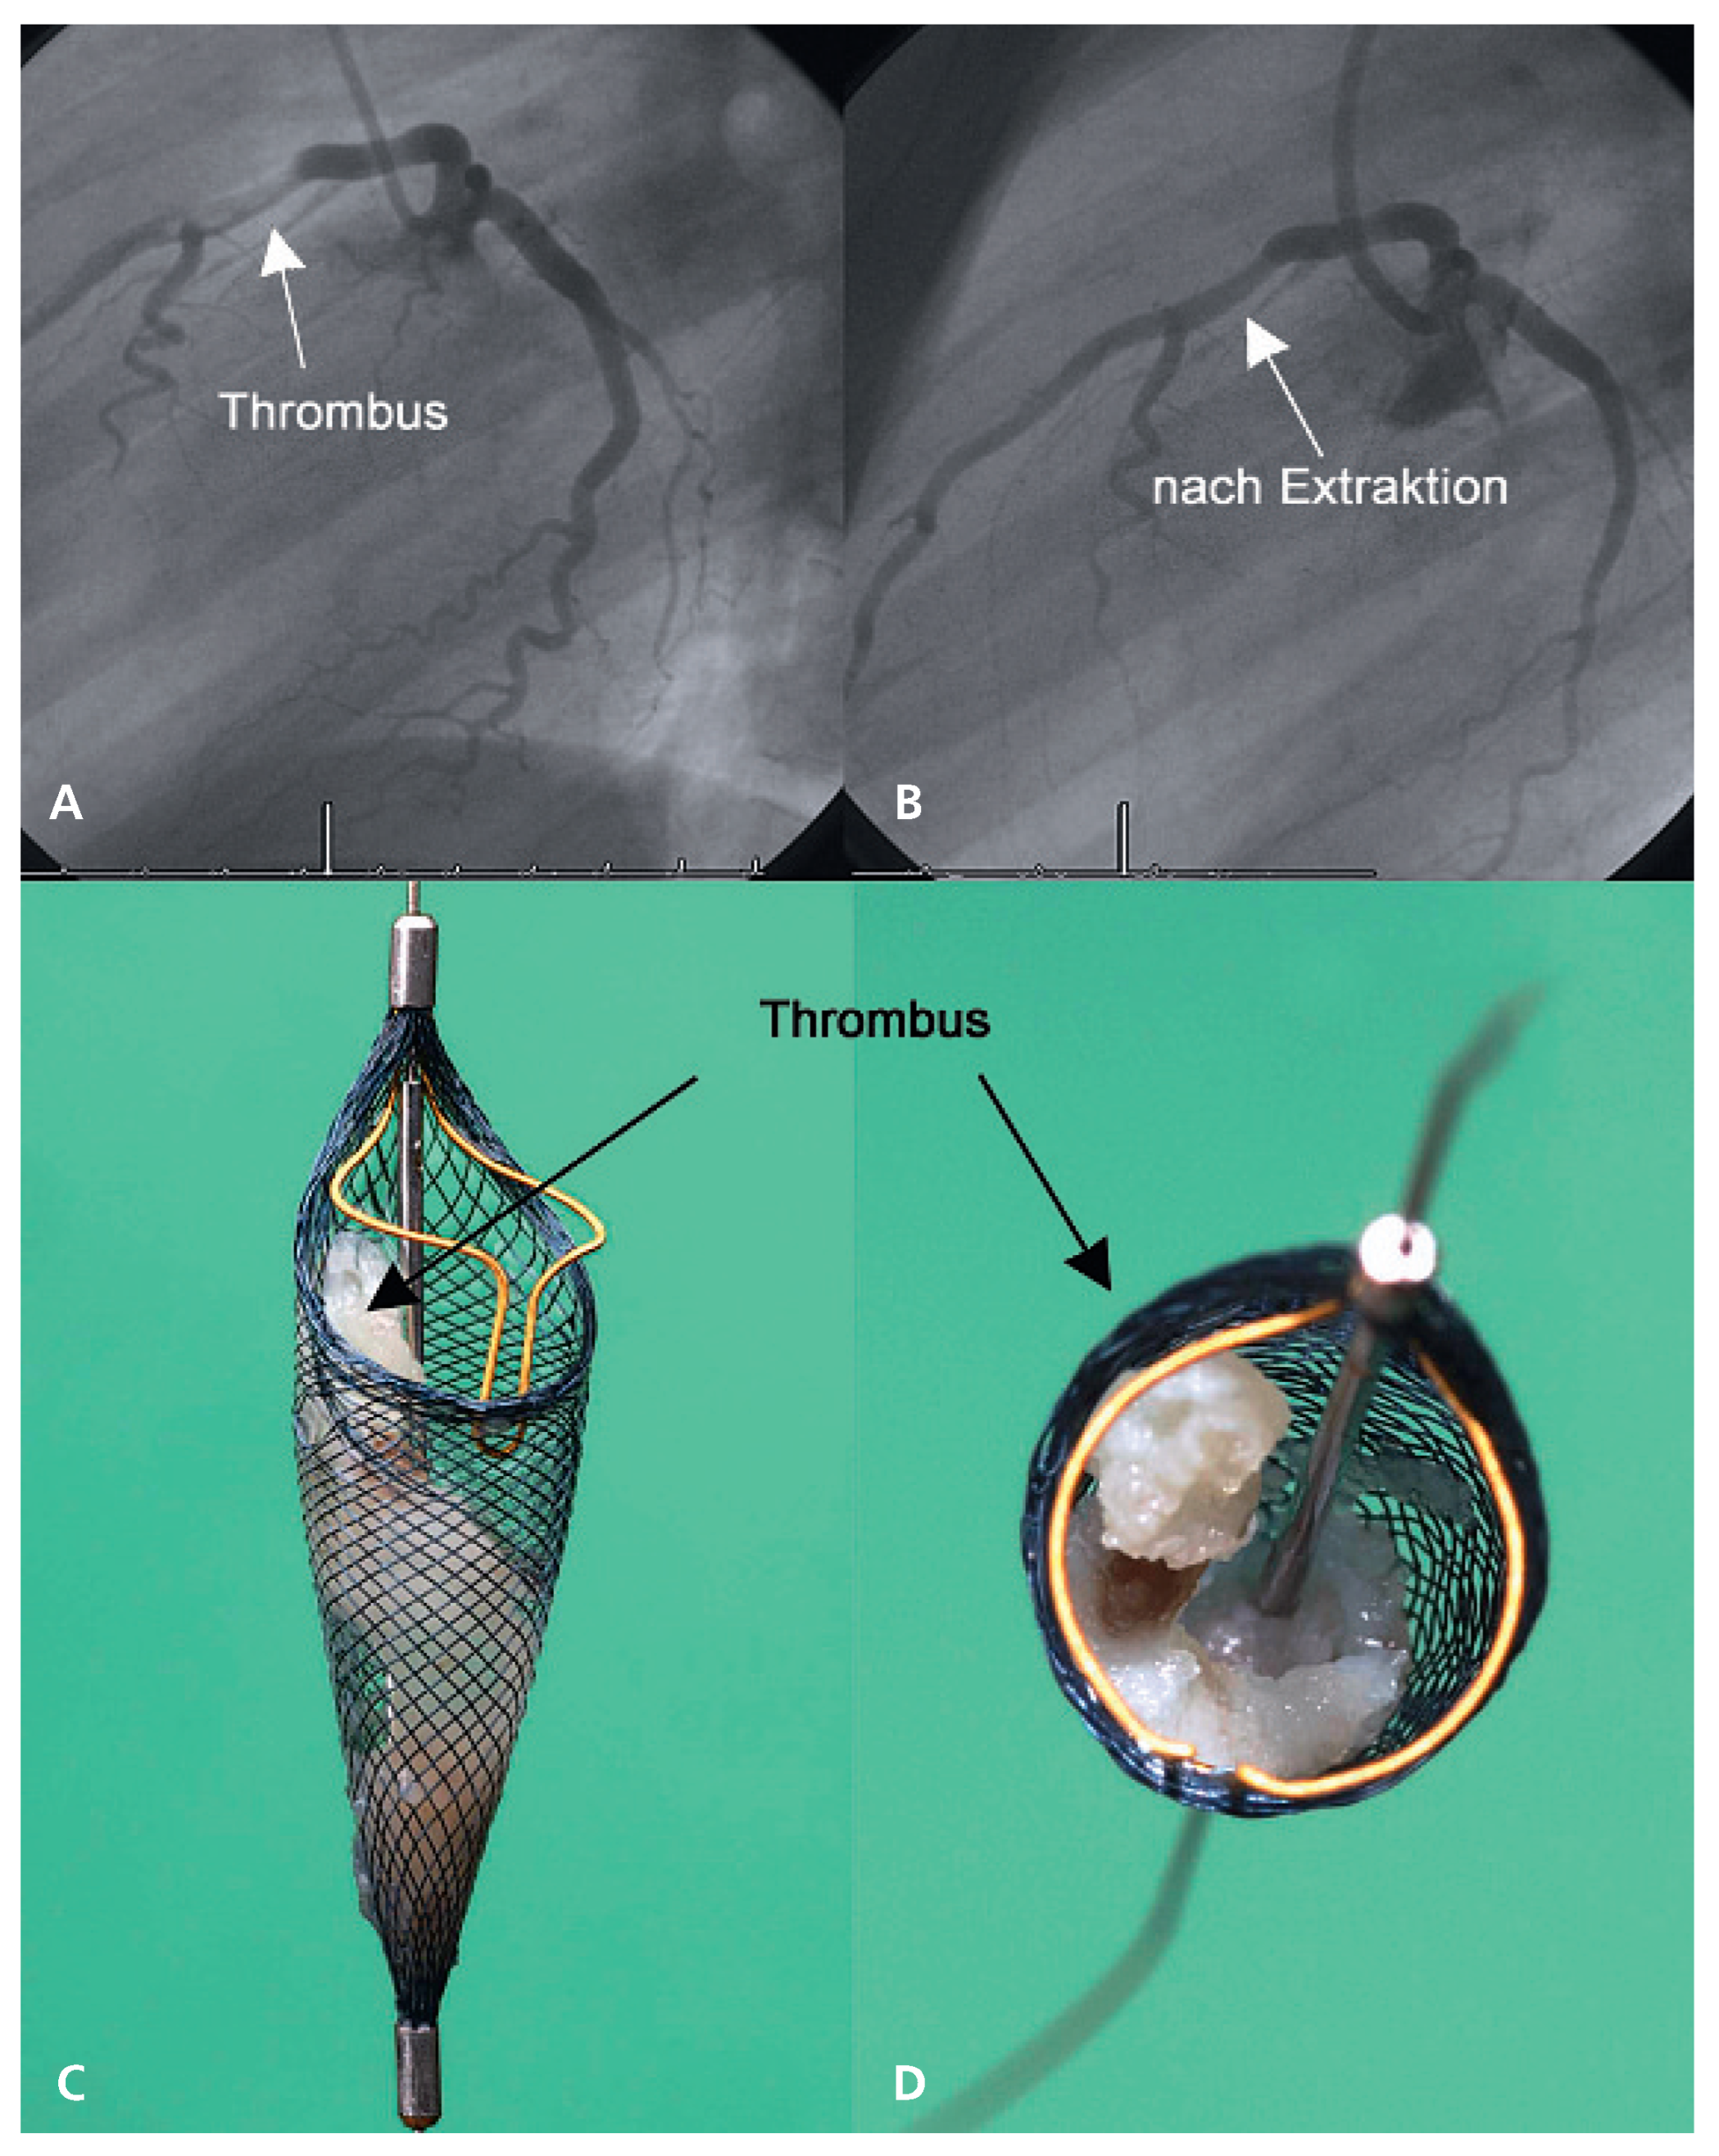

Acute myocardial infarction

- Surder, D.; Kucher, N.; Eberli, F.R.; Roffi, M. Intracoronary thrombus in a 26-year-old man. Eur Heart J. 2006, 27, 2631. [Google Scholar] [CrossRef] [PubMed]